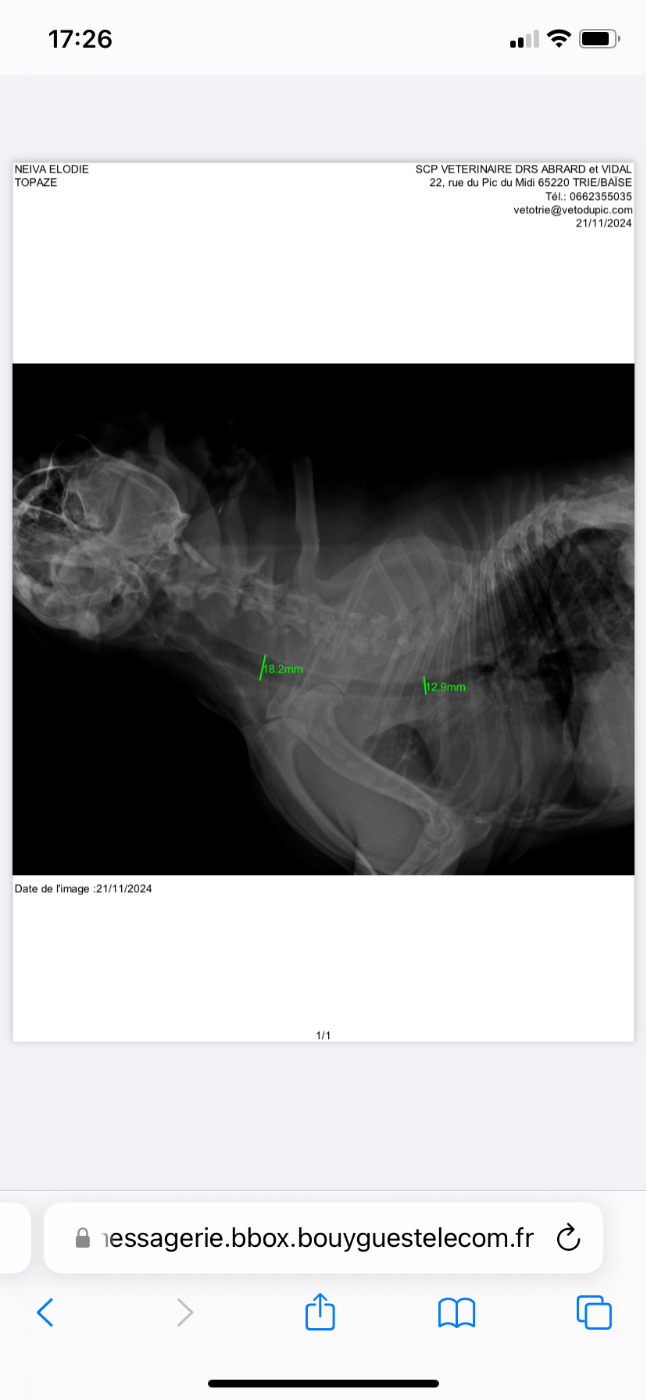

U topaze du comte de batz de castelmore

21/11/2024 - Trie sur Baïse ( 65220 ) Dépistage d hypoplasie de la trachée

Juge : Docteur Vidal

Absence d hypoplasie de la trachée avec comme mesures entre 18 et 13 mm